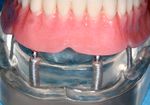

الجراحات التعويضية للتركيبات الغير ثابتة

وفي الأسواق اليوم نماذج كثيرة من الزرعات التيتانية التي أصبحت الشكل الوحيد المقبول للتعويض عن فقدان الأسنان، وهناك تقنيات عدة لتثبيتها منها ما يعتمد على الغرس بطورين من الزمن؛ تبقى الزرعة في الطور الأول مطمورة في العظم ويثبت الجزء البارز من اللثة في الطور الثاني، ومنها ما يأخذ شكله النهائي مباشرة في عمل جراحي واحد. وتثبت الإحصاءات نجاح النمط الأول بنسبة أعلى من النمط الآخر.